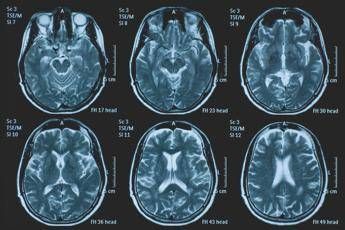

(Adnkronos) – La Commissione europea (Ce) ha autorizzato la commercializzazione condizionata di tovorafenib come monoterapia per il trattamento dei pazienti di età pari o superiore a 6 mesi con glioma pediatrico di basso grado che presentano una fusione o un riarrangiamento del gene Braf o una mutazione Braf-V600, in progressione di malattia dopo una o più terapie sistemiche precedenti. Lo annuncia Ipsen, in una nota, precisando che si tratta della “prima terapia mirata” per questa patologia e che la decisione della Ce si riferisce ai 27 Stati membri della Ue, oltre a Islanda, Liechtenstein e Norvegia. Ogni anno in Ue vengono diagnosticati più di 800 nuovi casi di glioma pediatrico di basso grado (pLgg) con alterazione di Braf. Questo tumore cerebrale, nonostante sia classificato di basso grado (a lenta progressione), comporta un carico significativo e permanente che accompagna la persona per tutta la vita, causando spesso importanti compromissioni fisiche e neurologiche, tra cui perdita della vista, difficoltà di linguaggio e disfunzioni motorie, che possono incidere in modo significativo sull’istruzione, l’autonomia e la qualità di vita a lungo termine del bambino. Finora, molti bambini con pLgg hanno dovuto sottoporsi a interventi chirurgici invasivi, a più cicli di chemioterapia e a radioterapia, con conseguenti complicazioni della salute. “Per i piccoli che ricevono la diagnosi di glioma di basso grado, il percorso è spesso lungo e difficile, con opzioni terapeutiche limitate – afferma Sandra Silvestri, Executive Vice President and Chief Medical Officer, Ipsen – Questa approvazione rappresenta un passo avanti significativo per questi bambini e per le loro famiglie, rafforzando al contempo il nostro impegno a rispondere a elevati bisogni clinici non soddisfatti. Ora il nostro obiettivo è garantire che i bambini eleggibili in tutta Europa possano accedere a questa terapia il più rapidamente possibile”. L’approvazione della Ce si basa sui dati dello studio di fase 2 Firefly-1 che ha valutato tovorafenib in 137 bambini e giovani adulti con pLgg recidivato o refrattario con alterazioni di Braf che avevano ricevuto almeno una precedente terapia sistemica. Nel dettaglio, lo studio ha dimostrato una risposta tumorale clinicamente significativa con un tasso di risposta globale del 71% secondo i criteri Rano-Hgg (ResponseAssessment in Neuro-Oncology criteria for High-Grade Gliomas) e del 53% secondo i criteri Raono-Lgg (Response Assessment in Paediatric Neuro-Oncology for Low-Grade Glioma), con un tasso di beneficio clinico del 77% secondo i criteri Rano-Hgg e del 58% secondo i criteri Rapno-Lgg. Le risposte – riferisce la nota – sono state rapide e durature: sulla base dei criteri Rapno-Lgg, tra coloro che hanno risposto, il tempo mediano alla risposta è stato di 5,4 mesi con una durata mediana della risposta di 18 mesi. Sul profilo di sicurezza, tovorafenib è stato generalmente ben tollerato, con eventi avversi legati al trattamento (Traes) prevalentemente di grado 1 o 2 e un tasso di interruzione basso (9,5% dei pazienti ha interrotto il trattamento a causa di eventi ritenuti dallo sperimentatore correlati a tovorafenib). I Traes più comuni comprendevano variazione del colore dei capelli, creatinfosfochinasi ematica alta, fatigue, anemia, vomito, ipofosfatemia, cefalea, eruzione cutanea maculopapulare, febbre, ritardo della crescita, secchezza cutanea. Il regime posologico semplice, con la somministrazione orale una volta alla settimana, con o senza cibo, in formulazione liquida o in compresse, ha ridotto al minimo i disagi nella routine quotidiana. Le famiglie con piccoli colpiti dal glioma di basso grado “spesso devono affrontare anni di incertezza, difficili decisioni terapeutiche e il timore delle conseguenze a lungo termine”, evidenzia François Doz, professore di Pediatria alla Paris Descartes University, vicedirettore di Clinical Research, Innovation and Teaching al Siredo Oncology Centre of the Curie Institute (Assistenza, innovazione e ricerca nel campo dei tumori dell'infanzia, dell'adolescenza e dei giovani adulti) e direttore didattico dell’Hospital Ensemble of the Institut Curie. Il regolamento dell'Ue sulla valutazione delle tecnologie sanitarie (Health Technology Assessment – Hta -Regulation), la cui attuazione è iniziata progressivamente a partire da gennaio 2025 – conclude la nota – ha introdotto un nuovo processo di valutazione clinica congiunta (Joint Clinical Assessment – Jca) volta a semplificare e armonizzare la revisione comparativa delle evidenze cliniche negli Stati membri dell'UE. Tovorafenib è il primo farmaco a essere sottoposto a una valutazione Jca.